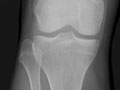

You may also have an X-ray (such as an X-ray of the hip or knee) or other imaging tests to check for joint damage.